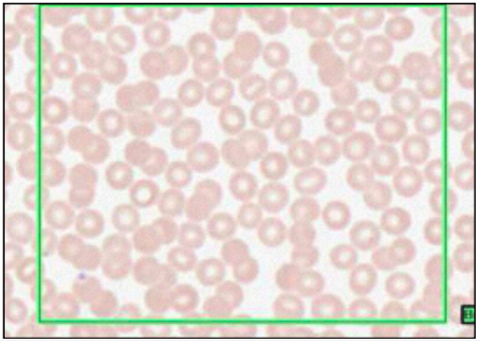

RBC (LEISHMAN’S STAIN - TYPE OF ROMANOVSKY SMEARS)

- 44% of blood

- anucleate - leads to biconcavity

- 120 day lifespan

RETICULOCYTES

- mature RBC loses cytoplasm and nucleus

- reticulocytes = immature RBC w/ some visible ribosomes, ie. some dark staining granules

- increased number with increased RBC produciton